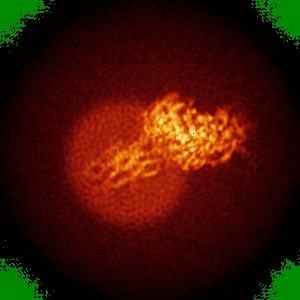

Cryo-EM structure of human GABA(B) receptor bound to the positive allosteric modulator rac-BHFF

Sample: Gamma-aminobutyric acid type B receptor

Structural Basis for Activation of the Heterodimeric GABA B Receptor.

Kim Y, Jeong E, Jeong JH, Kim Y, Cho Y

(2020) J Mol Biol , 432 , 5966 - 5984